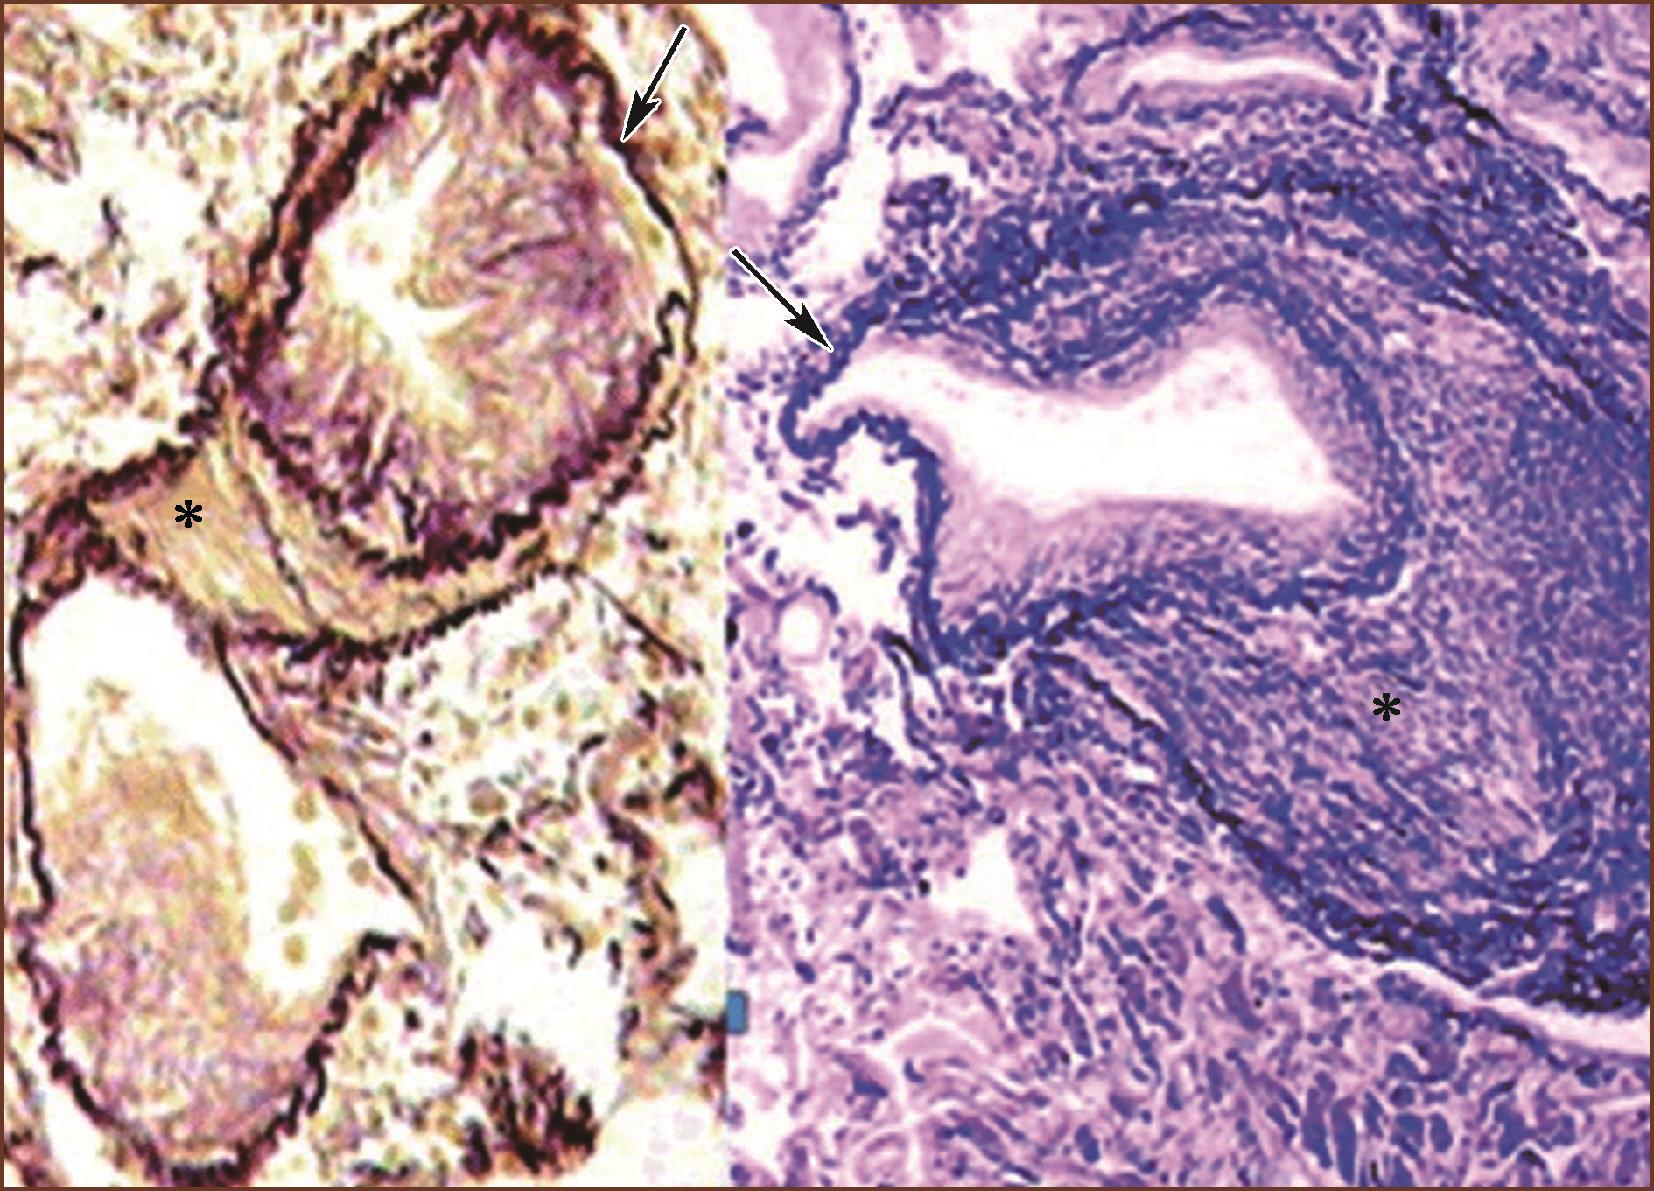

肺动脉-静脉瘘(pulmonary arteriovenous fistulae)为肺动脉、静脉之间先天性连接异常。患者开始无症状,以后出现呼吸困难、发绀、咯血。血管分流一般是右到左,但如支气管动脉也参与了此种畸形,可见双向分流。肺内可见扩大的但大、小不一的囊腔或血管腔,由薄壁类似静脉的宽大、但大小不一、形状不规则的血管形成。在组织切片上可见宽大肥厚的肺肌型动脉,纵切呈多枝状。肺肌型动脉与支气管、细支气管无关系。也可见到大小不一的静脉与动脉直接互相沟通,在弹力染色的切片上显示一侧为肥厚的动脉、有双层弹力板,另一侧为静脉样结构(图3-1-18)有的病例可见内含许多扩大、薄壁的丛状血管(telangiectases)。肺动脉-静脉瘘多在外科标本(一肺段或肺叶内)被发现,很少见于肺活检标本。肺动-静脉瘘继发慢性肺动脉高压后可见肺小动脉中层肥厚、内膜纤维化,新旧血栓形成,管腔狭窄。也可产生肺小静脉内膜纤维化,新旧血栓形成;但未见丛状病变。在临床上肺动脉-静脉瘘有的被误为先天性心脏病,有的被误为慢性肺结核。

图3-1-18 肺小动脉一侧明显不均匀性增厚(∗),另一侧壁薄似静脉(箭头所示),内膜轻度纤维化(ET+VG, ×200)